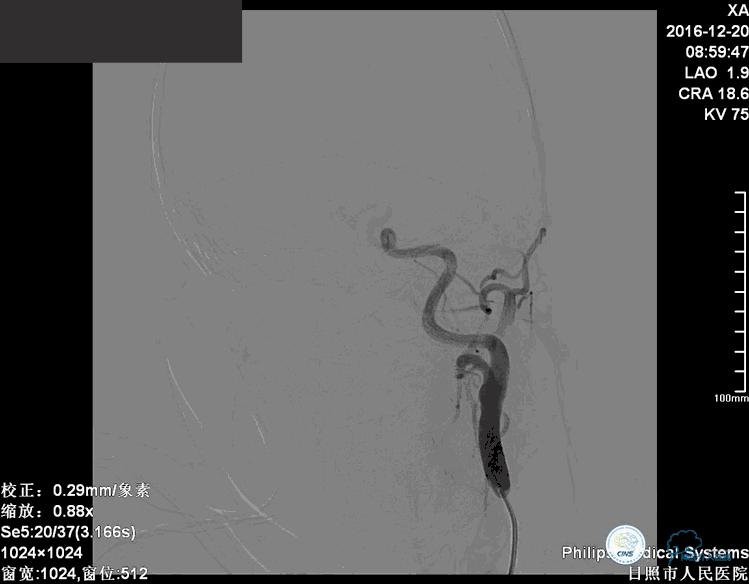

确诊:基底动脉顶端宽颈未破裂动脉瘤,动脉瘤大小约6mm×9mm,瘤颈约4毫米。

注:以下为动图